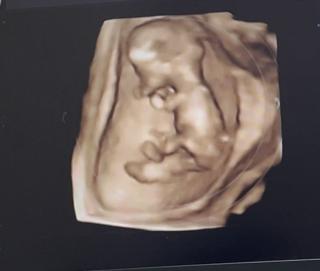

12wの検診で今日から腹部エコーでした。5.1cm。心臓の音も聞かせてもらいました。3人目にして初の3Dエコー。凄い感動!早く会いたいなぁ。次からは4週毎の検診です。